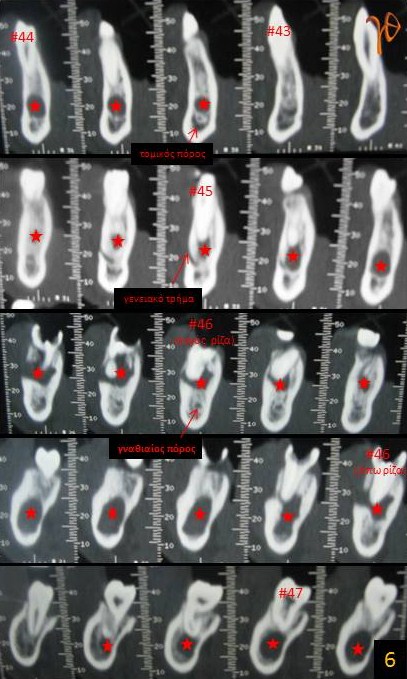

Πολύχωρη κύστη κάτω γνάθου(Εικ. 5 και 6).

6

Εικ. 6: Στις κάθετες τομές της υπολογιστικής τομογραφίας απεικονίζονται με ακρίβεια οι τοπογραφικές σχέσεις των κυστικών χώρων(άστρα) με τα ακρορρίζια των δοντιών(#43-#47), τον γναθιαίο πόρο, το γενειακό τρήμα και τον τομικό πόρο.